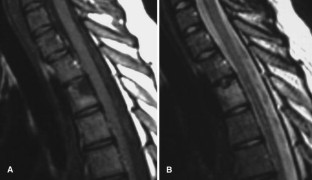

SAPHO: syndrome or concept? Imaging findings

The SAPHO syndrome was a term coined to include a variety of musculoskeletal disorders associated with skin conditions, mainly palmoplantar pustulosis and acne conglobata. It is more correctly a spectrum which includes the following: skin lesions, osteoarticular manifestations of synovitis hyperostosis and osteitis affecting particular target sites, and·a clinical course marked by relapses and remissions. The major sites of involvement are the anterior chest wall, the spine, long bones, flat bones, and large and small joints. The distribution and severity of involvement varies from the adult to the pediatric form of chronic recurrent multifocal osteomyelitis (CRMO). The diagnosis of SAPHO syndrome is not difficult when the typical osteoarticular lesions are located in characteristic target sites. The diagnosis is more difficult if atypical sites are involved and there is no skin disease.